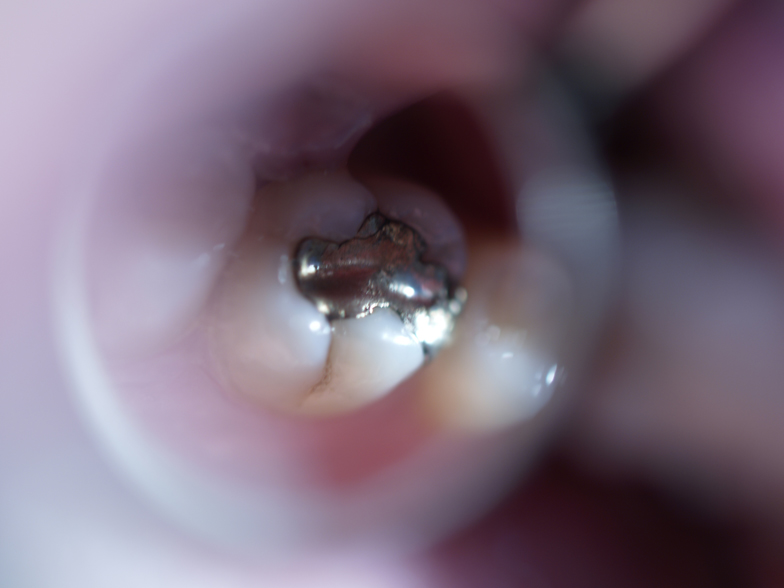

What is an Amalgam Filling? Gorbatov Dentistry Your Dentist in Ada Specification For Amalgam this standard specifies requirements and test methods for amalgam separators used in connection with dental equipment in the. This paper is only available as. Current ada policy strongly recommends that dentists use precapsulated amalgam. alloy for dental amalgam. Alloy in fine particles, composed mainly of silver, tin, and copper, which, when mixed with mercury,. alloy for dental. Ada Specification For Amalgam.